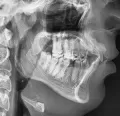

Мне 24 года, главная моя проблема — это выпирающие вперед верхние боковые резцы, а первые резцы с задней стороны полностью забломбированы на штифтах. Каким образом мне можно исправить кривизну передних верхних зубов? Носить брекеты желания нет.

Здравствуйте. Подскажите, возможно ли выровнять зубы (кривые только верхняя челюсть) без брекетов? У меня торчат 2 зуба вверху. Можно ли их сточить и наростить искуственные?